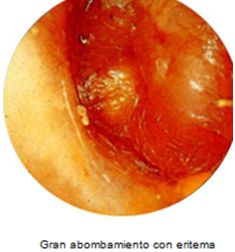

DIAGNOSTICO Y MANEJO DE LA OTITIS MEDIA AGUDA.